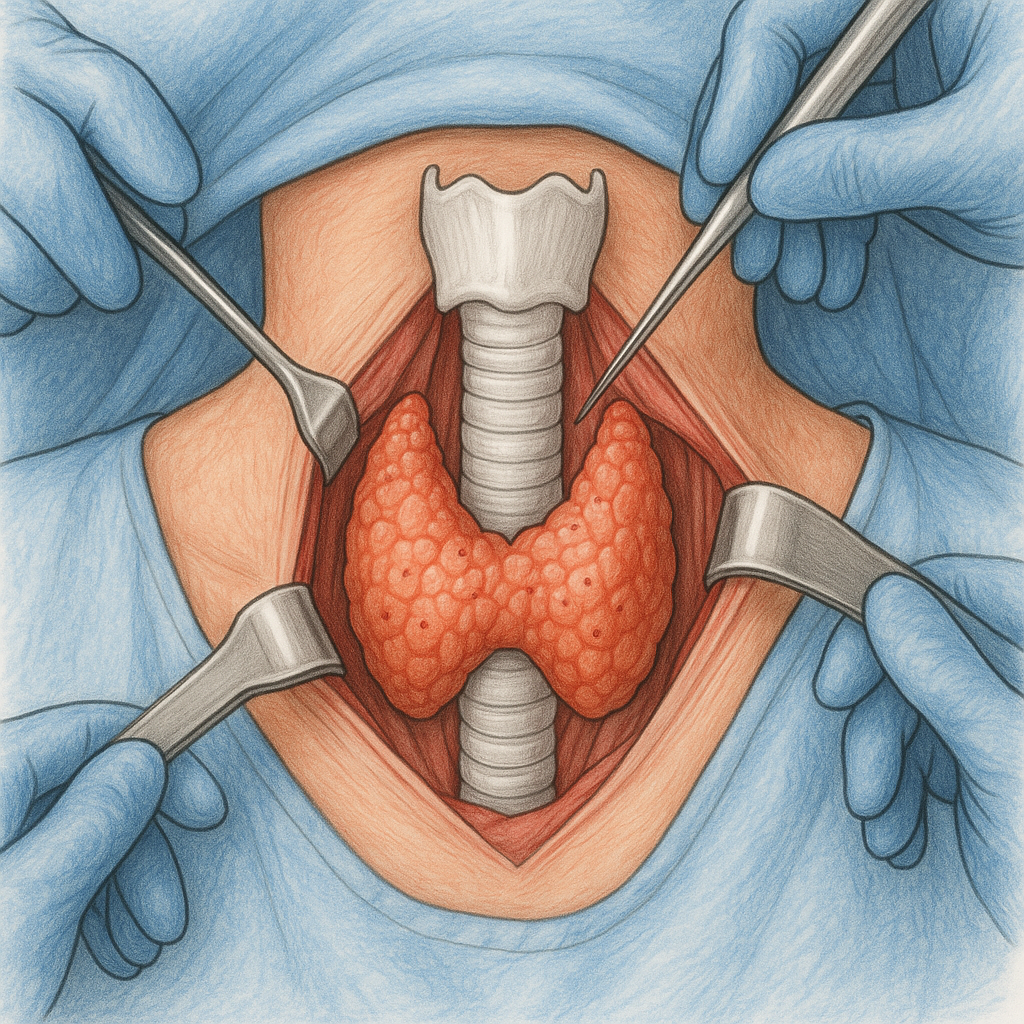

Breast Cancer Surgery & Care

General & Laparoscopic Surgery